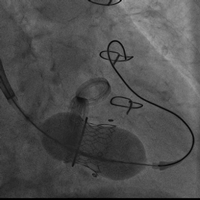

病例二(经心尖二尖瓣瓣中瓣)

患者女性,60岁,既往行二尖瓣生物瓣置换术,置入HANCOCK II 25#瓣膜一枚。STS评分8.18 %,属于外科换瓣手术高风险患者。术前心脏超声示原二尖瓣生物瓣衰败,瓣叶明显脱垂,关闭极差,可及大量反流。术前充分评估,经心尖途径植入23# Renato球扩式瓣中瓣,释放成功后瓣膜功能良好,无明显瓣中及瓣周反流,平均跨瓣压差2.6mmHg。

瓣膜释放 术后左室造影